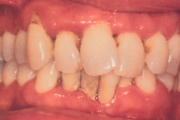

- igemepiir on taandunud (3)

- hammaste asukoha muutus (5)

- vahed hammaste vahel (5)

- hammaste tundlikkus (9)